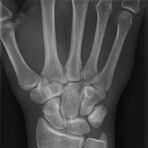

Konventionelles Röntgen

Der Begriff Röntgen, oder auch Röntgendiagnostik bezeichnet ein Verfahren in der Radiologie, bei dem von einer Röntgenröhre elektromagnetische Wellen (Röntgenstrahlen) durch die zu untersuchende Körperregion des Patienten gesendet werden. Je nach Dichte der Gewebeart des Körpers (z.B. Knochen oder Lunge) werden die Röntgenstrahlen im Körper unterschiedlich stark abgeschwächt. Ein digitaler Detektor empfängt dann die Röntgenstrahlen, die in abgeschwächter Form den Körper wieder verlassen haben. Daraus wird das Röntgenbild erzeugt.

Die Röntgenuntersuchung ist weiterhin eine unverzichtbare Basisdiagnostik. Viele Fragen können in der medizinischen Diagnostik mit einer konventionellen Röntgenaufnahme geklärt werden.